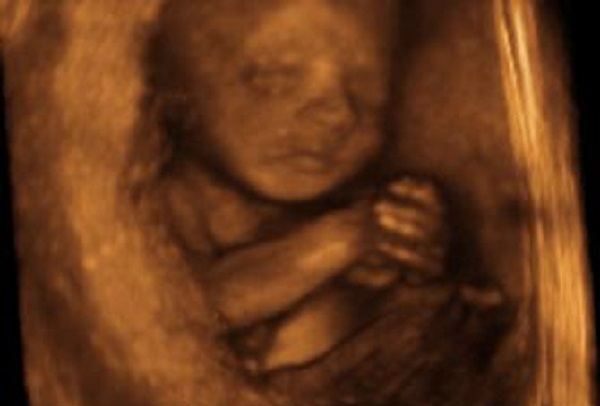

Abortion Clinics Harvest Scalps of Aborted Babies, Sell Them to Researchers Treating Baldness

Harvesting Baby Body Scalps to Treat Baldness?

A former board director for the Center for Medical Progress testified during the civil trial in the San Francisco Federal District Court that the scalps of babies provided by the abortion industry are being harvested for research in treating baldness.